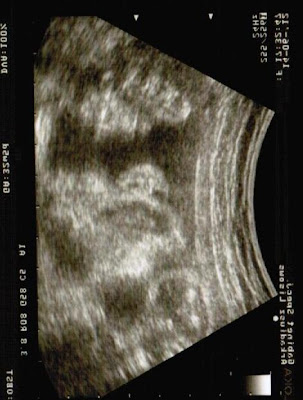

A niżej aktualne fotki Gabi

| Gabi z profilu |

| Tutaj widać Gabi nosek i usta |